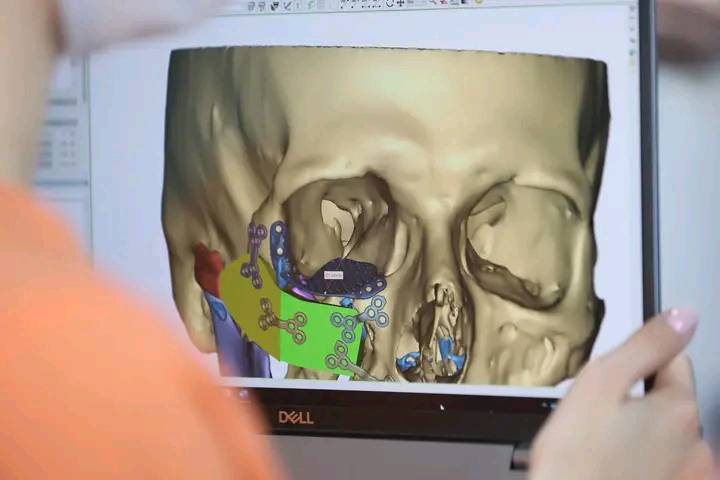

Протягом чотирьох днів на Івано-Франківщині команди хірургів та медсестер з Канади, США та України провели 83 оперативні втручання для 26 військовослужбовців з важкими пораненнями. Медична місія була організована в рамках проєкту Face the future.

Як зазначили в КНП ОКЛ Івано-Франківської обласної ради, з-поміж 800 пацієнтів було відібрано три десятки військових, які потребували відновлення здоров’я, зокрема корекції пошкоджень вух, обличчя, пластики носа та відновлення фрагментів щелепи з використанням імплантів.

Для деяких військових це вже не перша участь у місії Face the future та чергова операція на шляху до відновлення. Для інших пацієнтів ця місія стала початком багатоетапного процесу реконструктивної хірургії.

У складі міжнародної команди працювали лікарі Івано-Франківської обласної клінічної лікарні, які об’єднали свої зусилля з іноземними колегами для надання висококваліфікованої медичної допомоги українським захисникам.